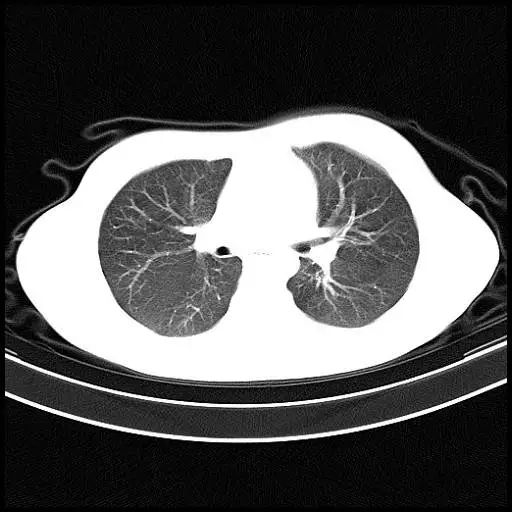

正常肺的CT表现